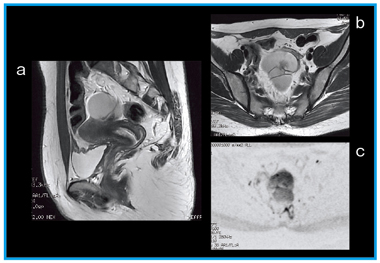

●体幹部(図3)

グラディエント能力の向上とB1のコントロールにより,DWIの画質が大きく向上した。体動補正技術である「PROPELLER」を用いることで,体幹部におけるT1強調画像や任意断面の撮像が可能になった。

図3 卵巣がん

a:T2強調画像 (PLOPELLAR,スキャン時間3分16秒)

b:T2強調画像 (アキシャル画像,スキャン時間2分20秒)

c:DWI(b値=1000,スキャン時間2分55秒)